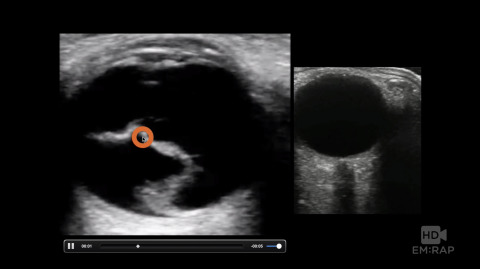

POCUS for Retinal Detachment

How to differentiate a retinal detachment from a vitreous detachment using bedside point of care ultrasound. Presented by Dr. Jacob Avila, MD.

1 chapterJune 2017